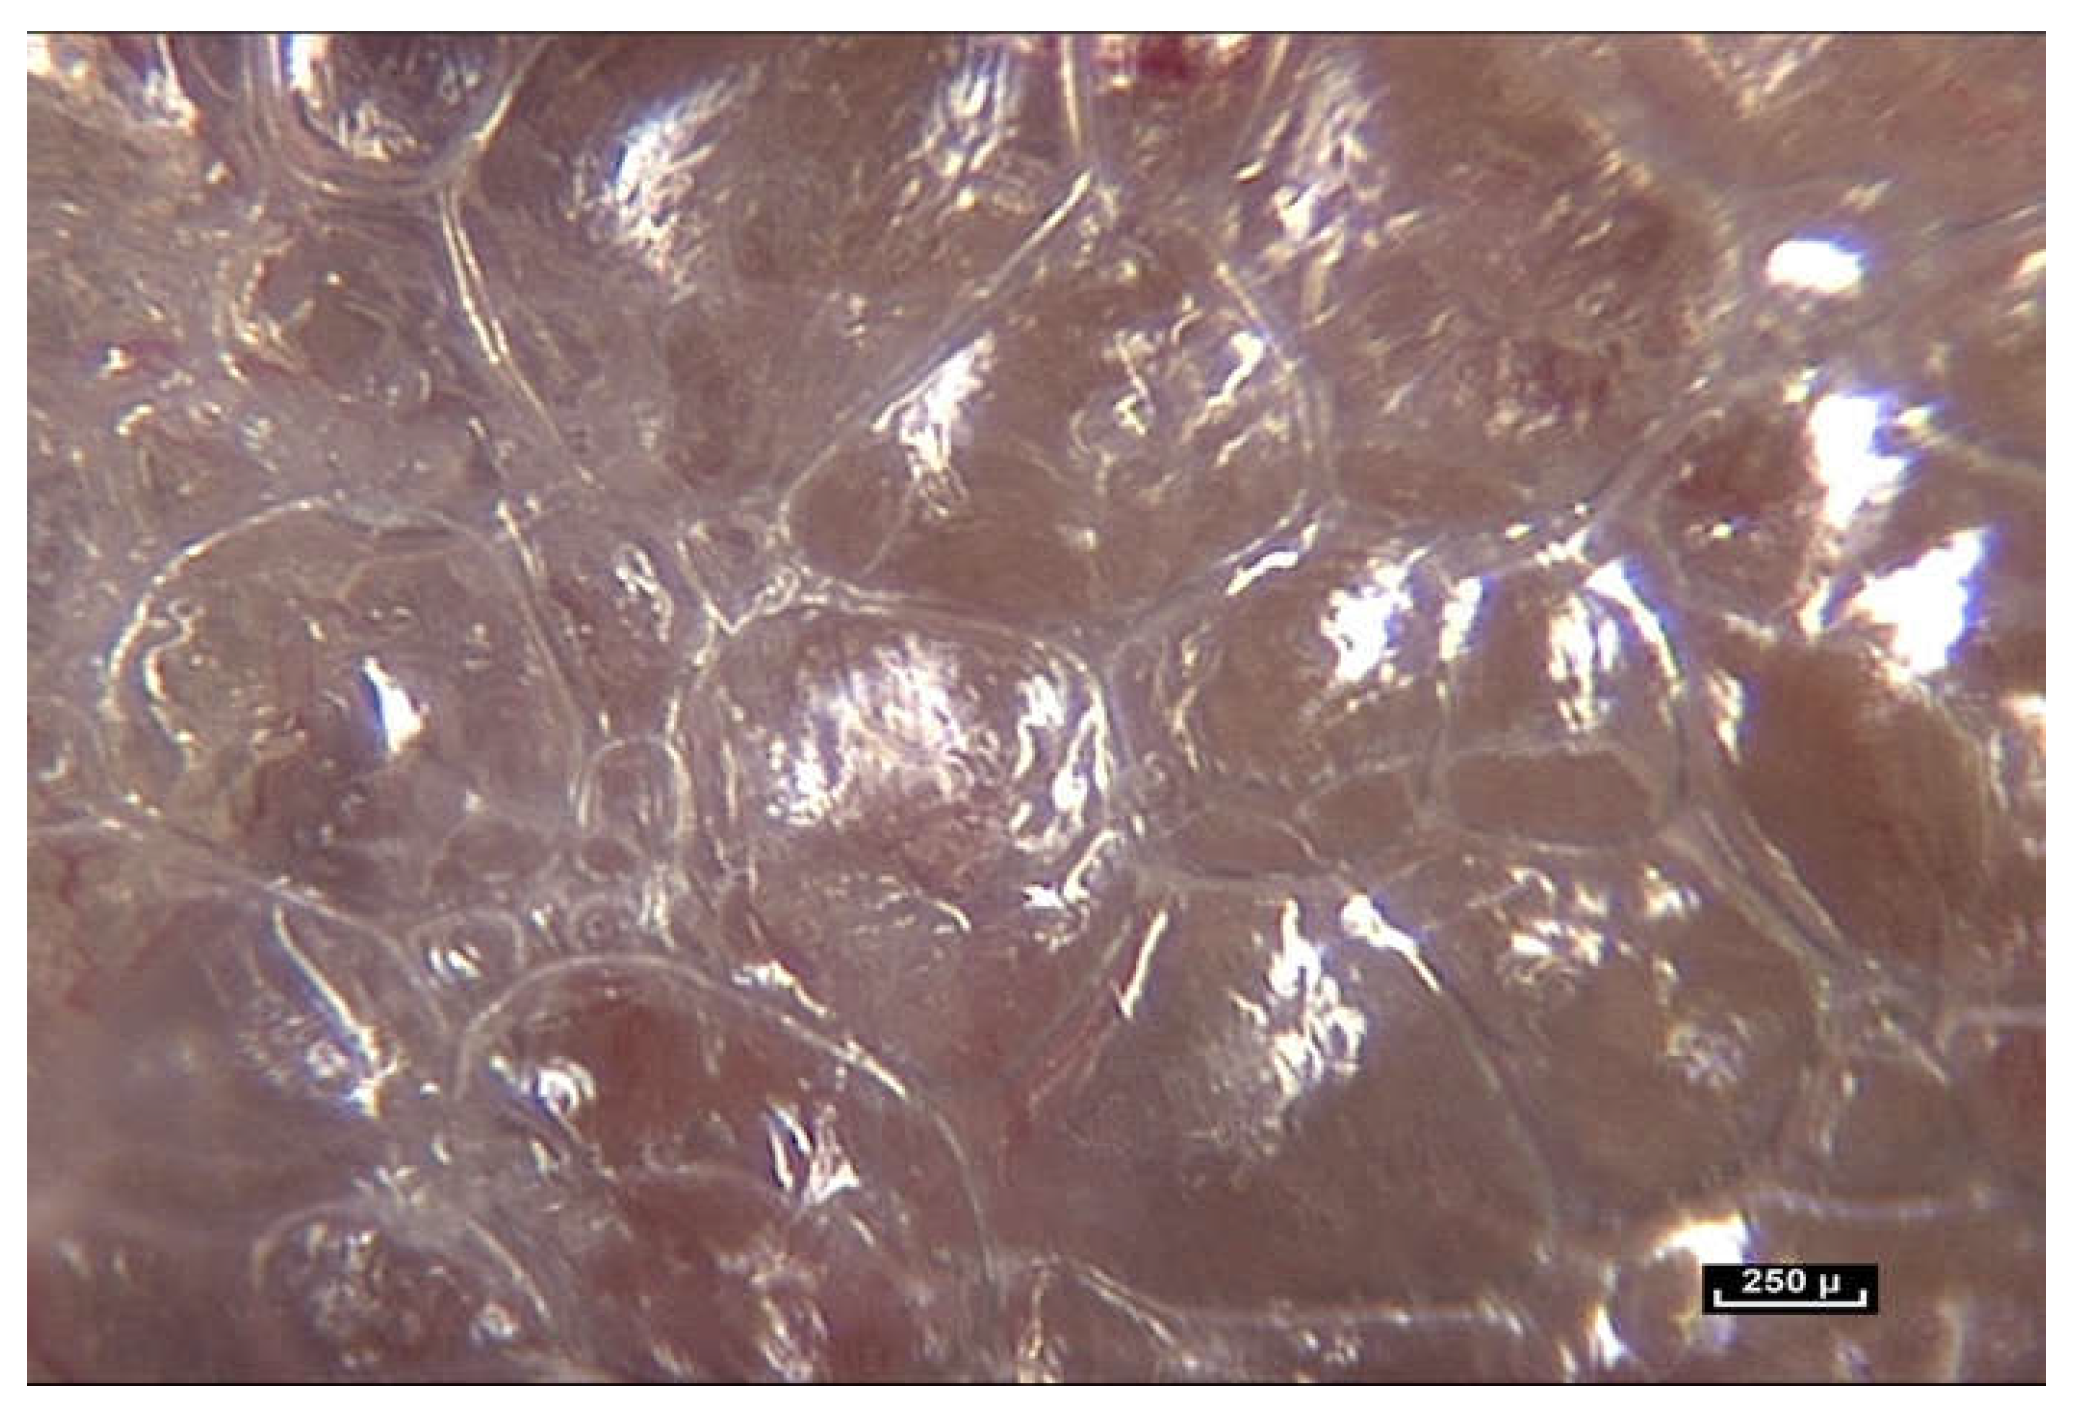

In our opinion, the notion of volume is crucial because it is closely linked to the notion of form. We have observed small polyhedral forms with surfaces that reflect the cold light emitted by the endoscope. This is a constant observation in the pre-“deep fascia” areas. Microvolumes are formed by the interweaving and intercrossing of fibers in three dimensions. They have irregular polyhedral shapes like everything seen so far—all different from one another. It is important to reiterate that any surgeon can see microvolumes during surgery. They are visible to the naked eye (Figure 13).

Figure 13. (Video S13) (×40 magnification) As we move the endoscope closer to these areas the light emitted by the endoscope is reflected from the glistening facets of the microvolumes, that resemble a pile of mirrors dumped arbitrarily in a heap. These forms that we see are polyhedral, irregular microvolumes but the physical status of a microvolume is itself unstable. Animated diagram to illustrate.